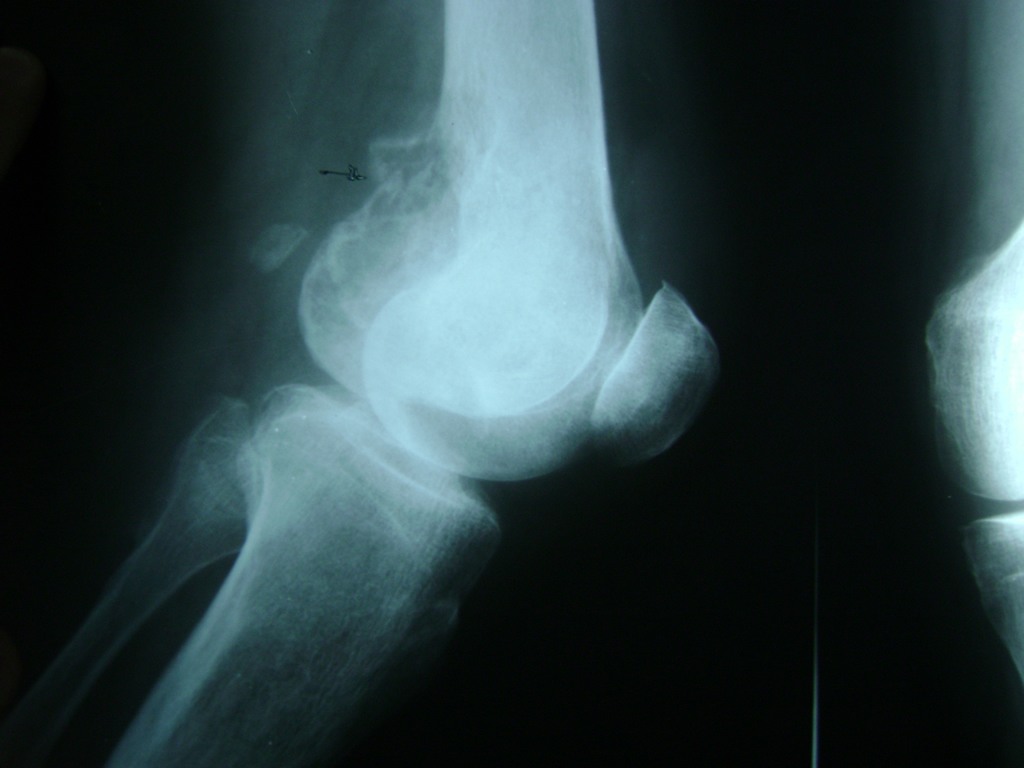

Fémur - Rodilla

La artroscopia de rodilla es un cirugía en el cual la estructura interna de la articulación es examinada ya sea para realizar un diagnostico o para realizar un tratamiento, este procedimiento se realiza utilizando un instrumento parecido a un pequeño tubo llamado artroscopio.